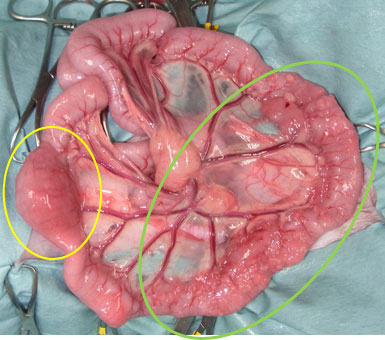

小腸に発生したリンパ腫:リンパ腫により腸閉塞を起こした症例

![]() 大きく腫れたリンパ腫(黄色丸)により腸閉塞を起こし、 |

![]() できる限りリンパ腫の浸潤している小腸を切除し、 |

![]() 切除された、小腸のリンパ腫 |